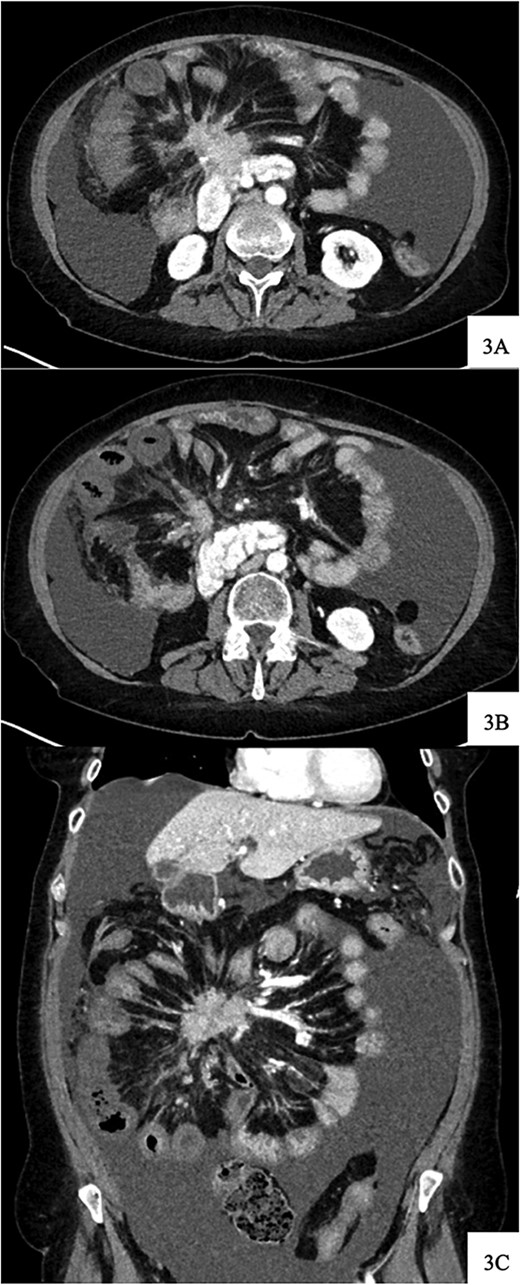

DOTATATE positron emission tomography-computed tomography scan revealing extent of metastatic disease.

Regarding her oncologic history, she was diagnosed with NET in October of 2017 when a computed tomography (CT) scan performed for intermittent abdominal cramping and diarrhea revealed a mass near the third portion of the duodenum and the root of the mesentery (Fig. 1). Biopsy of the mass revealed a well-differentiated NET. Further work-up with DOTATATE positron emission tomography (PET)/CT revealed a small bowel primary likely emanating from the terminal ileum as well as multiple lesions in the neck, chest, and liver (Figs 2 and 3). The periduodenal mass intimately involved the root of the mesentery, SMA, and SMV. She was initially treated with Lanreotide for many years with close monitoring and later underwent systemic treatment with Lutathera, a Peptide Receptor Radionuclide Therapy, from April 2020 to November 2020. She subsequently resumed Lanreotide in December of 2020, which she was on at the time of admission. Her disease remained largely stable on imaging over the next three years; however, her symptoms had been worsening over the few months leading up to her presentation.